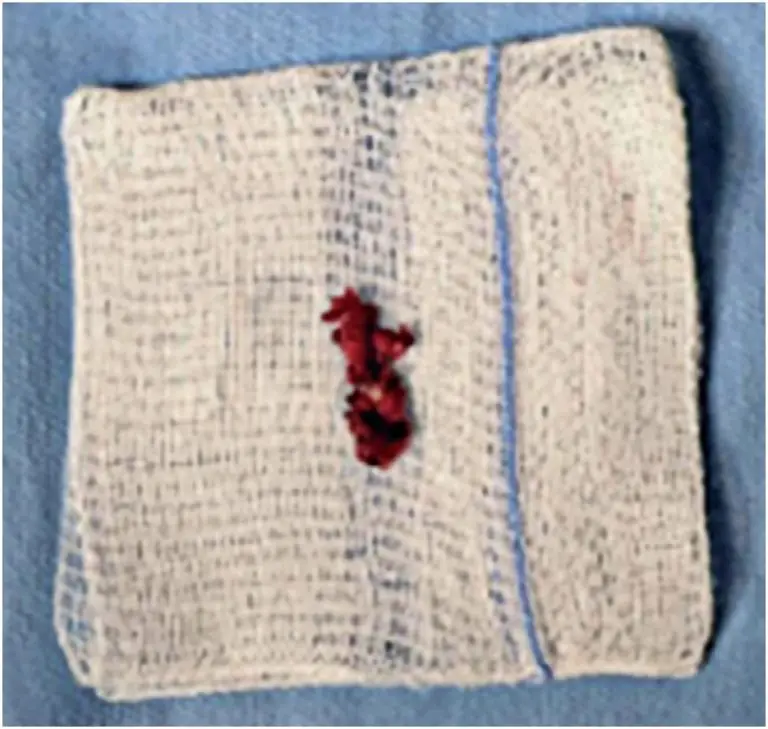

Lumbar synovial cysts are an uncommon cause of back pain and radiculopathy, usually manifesting with gradual onset of symptoms, secondary to involvement of the spinal canal. Rarely, intracyst hemorrhage occurs, and may acutely present as radicular – or even spinal cord – compression syndrome. Synovial cysts are generally associated with degenerative facets, although the pathogenesis has not been entirely established. We report a case of bleeding complication in a synovial cyst at L2-L3, adjacent to the right interfacet joint, causing […]